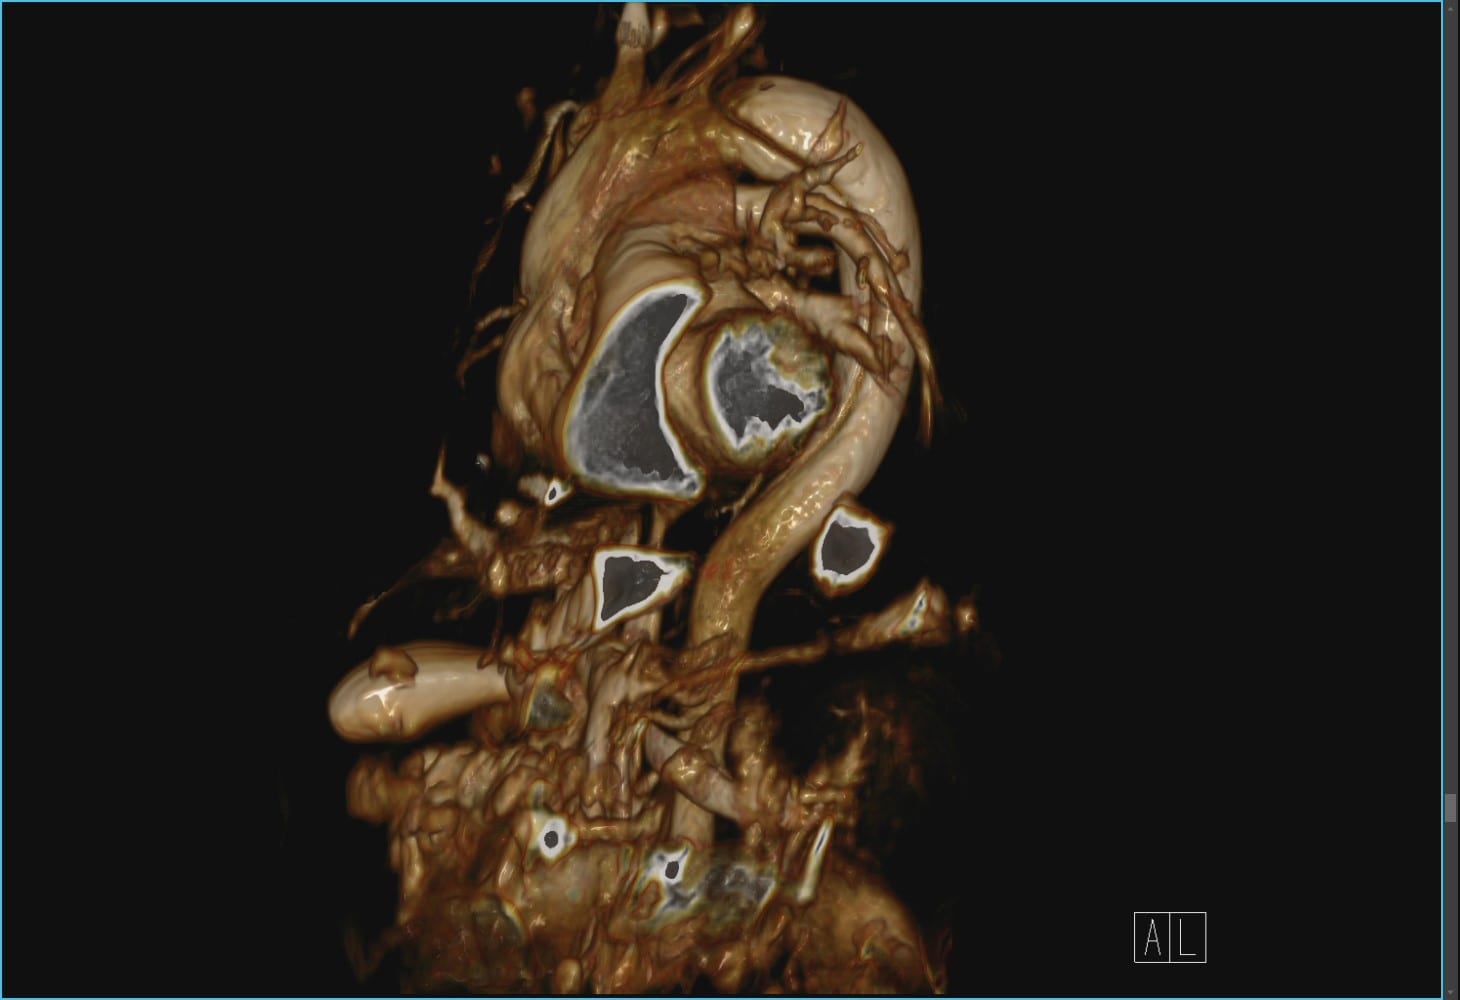

大動脈疾患の診断はCTを用いるのが一般的ですが、MRIは造影剤を用いないでも冠動脈を描出することや大動脈の血流動態の評価ができるので、造影剤アレルギーのある患者さんの血管診断に有効です。

慢性大動脈解離のMRI